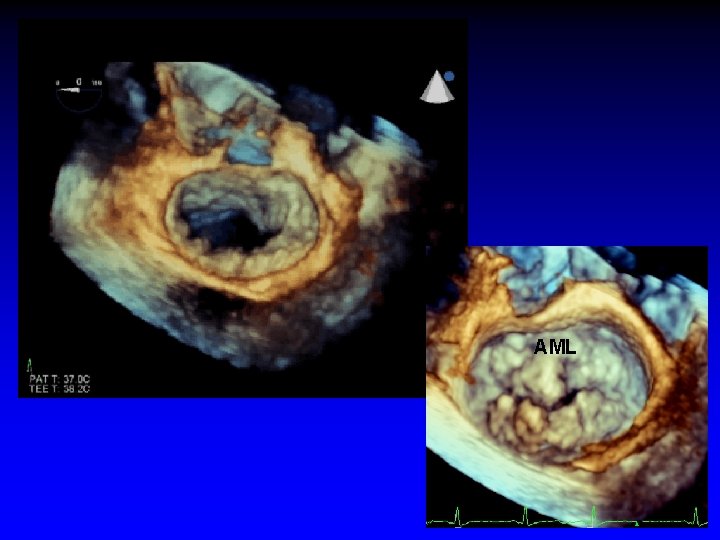

Case 4 Mitral Valve Prolapse

AML